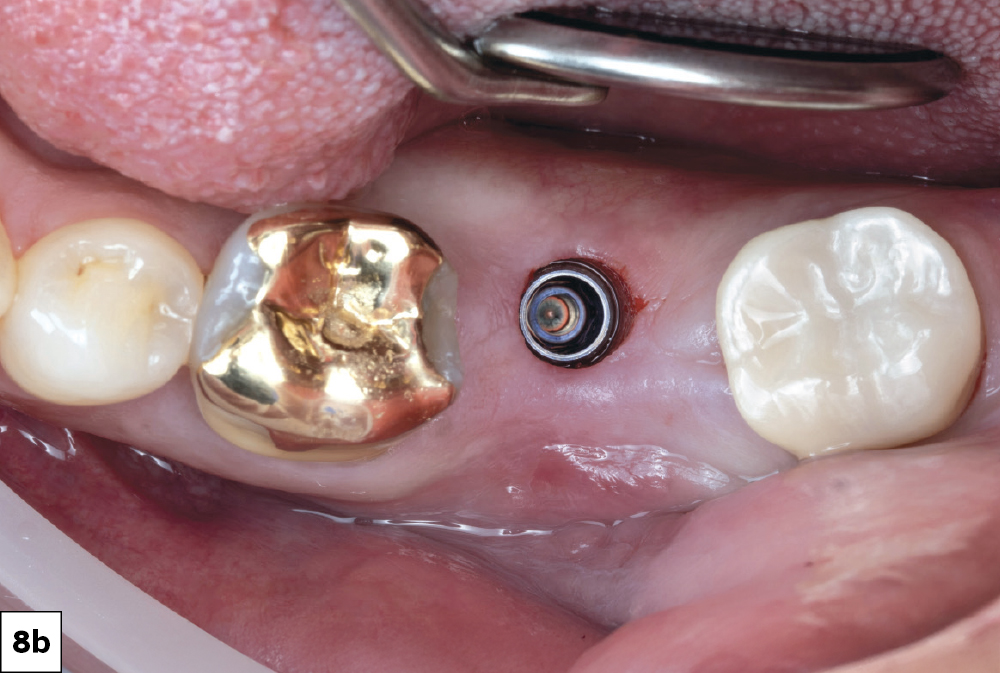

In-office milling is a quickly evolving option for the modern dental practice. With the introduction of a same-day screw-retained option, BruxZir® NOW SRC milling blocks, there’s even more opportunity for optimizing single-unit restoration workflows. In this case study, I’ll demonstrate how this product can be used as part of an efficient workflow for tooth replacement in the posterior. When combined with guided surgery and in-office crown design, this procedure offers reliable results while saving money and significantly cutting down on chair time for dentists.